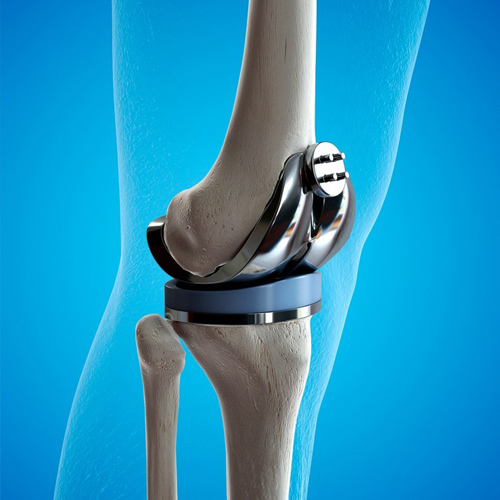

인공관절수술은 손상되거나 퇴행성 변화가 있는 관절을 인공 관절로 대체하는 수술입니다.

주로 무릎, 엉덩이, 어깨 관절에서 시행됩니다.

인공 재질로 된 관절로 바꾸어주는 수술입니다.

절제된 뼈의 표면에 맞추어 금속 및 특수 플라스틱 재질로 구성된 **인공관절 구성품(임플란트)**을 삽입하고 단단하게 고정합니다.